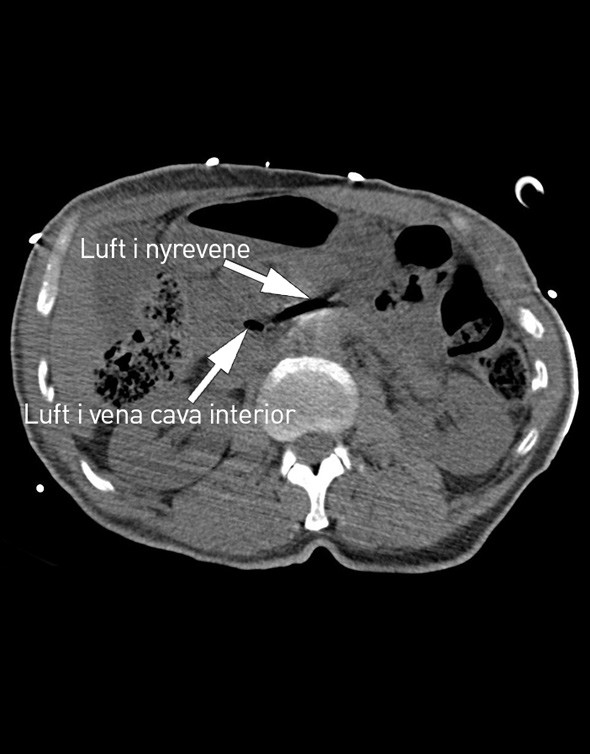

På sykehuset fikk han flere venekanyler i overekstremitetene. Den intraossøse nålen ble fjernet etter å ha vært åpen rundt en halvtime mens pasienten lå i sjokkleie. CT-undersøkelse av thorax, abdomen og bekken uten intravenøs kontrast tatt kort tid etter ankomst viste luft i høyre vena femoralis, vena cava inferior og venstre nyrevene. Sikker årsak til hjertestans ble ikke funnet, og pasienten døde etter et kort intensivopphold.